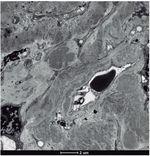

• Microscopia óptica: 11 glomérulos, 2 globalmente esclerosados, otros 2 con retracción del ovillo capilar, con plegamiento de las asas capilares y fibrosis pericapsular. Los restantes mostraron una prominente expansión de la matriz mesangial y de las paredes capilares por un material amorfo PAS (ácido peryódico de Schiff) positivo. Plata metenamina, negativo. Intersticio con moderada fibrosis intersticial, atrofia tubular acompañada de un infiltrado inflamatorio mono-nuclear restringido a dichas áreas (fig. 1).

Figura 1. Microscopio óptico: hematoxilina-eosina.